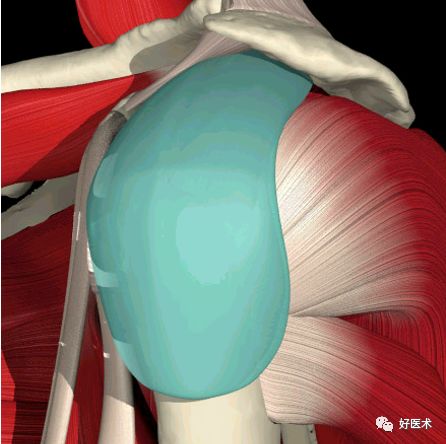

肩峰下囊:肩峰下囊是个潜在的空间

肩 袖:肩袖由四块肌肉和他们的肌腱组成

1. 肩胛下肌

2. 冈上肌

3. 冈下肌

4. 小圆肌